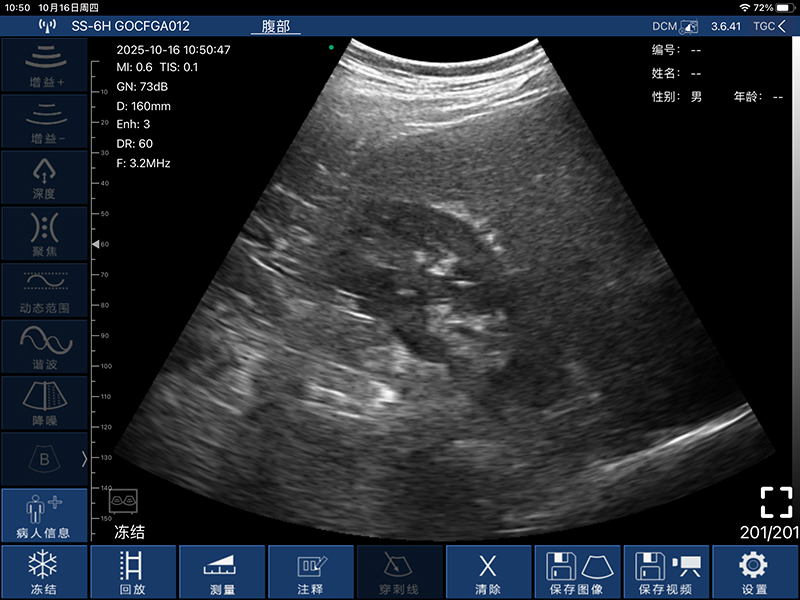

• 扫描方式:电子阵列扫描

• 探头频率:3.2/5.0MHz

• 扫描深度:90/160/220/305mm,可调

• 显示模式:B、B/M、Color、PW、PDI

• 图像调节:增益、焦点、反相脉冲谐波、降噪